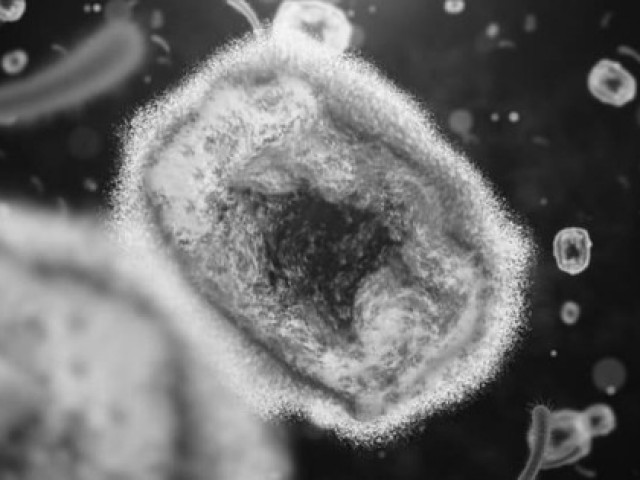

Mụn nước ở người bị đậu mùa khỉ.